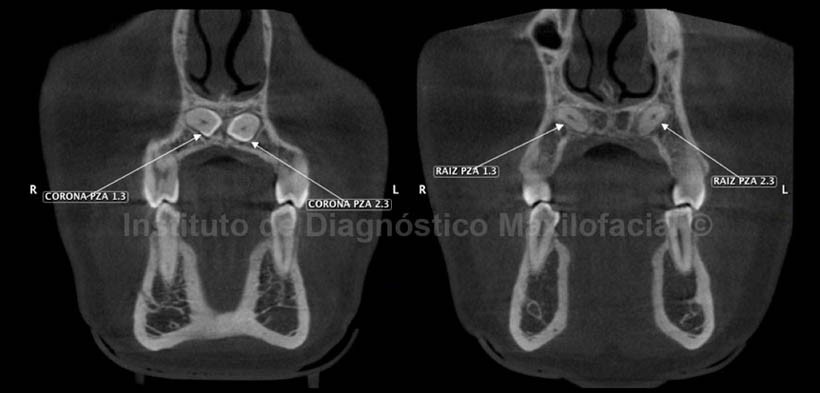

En cortes transaxiales (Fig. 2) se observa la corona de las pieza 1.3 próxima a la tabla vestibular, y su ápice en relación con la tabla palatina. Así mismo, la corona de la pieza 2.3 se observa próxima a la tabla palatina al igual que su ápice. En los cortes coronales (Fig.3) se observan las coronas de ambas piezas dentarias en estrecha relación con el conducto nasopalatino, el mismo que se observa parcialmente en esta imagen, además se aprecia la corona de la pieza 2.3 más inferior con respecto a la corona de la pieza 2.1 y el tercio medio radicular de ambas piezas se observa en relacioón con la cortical palatina.